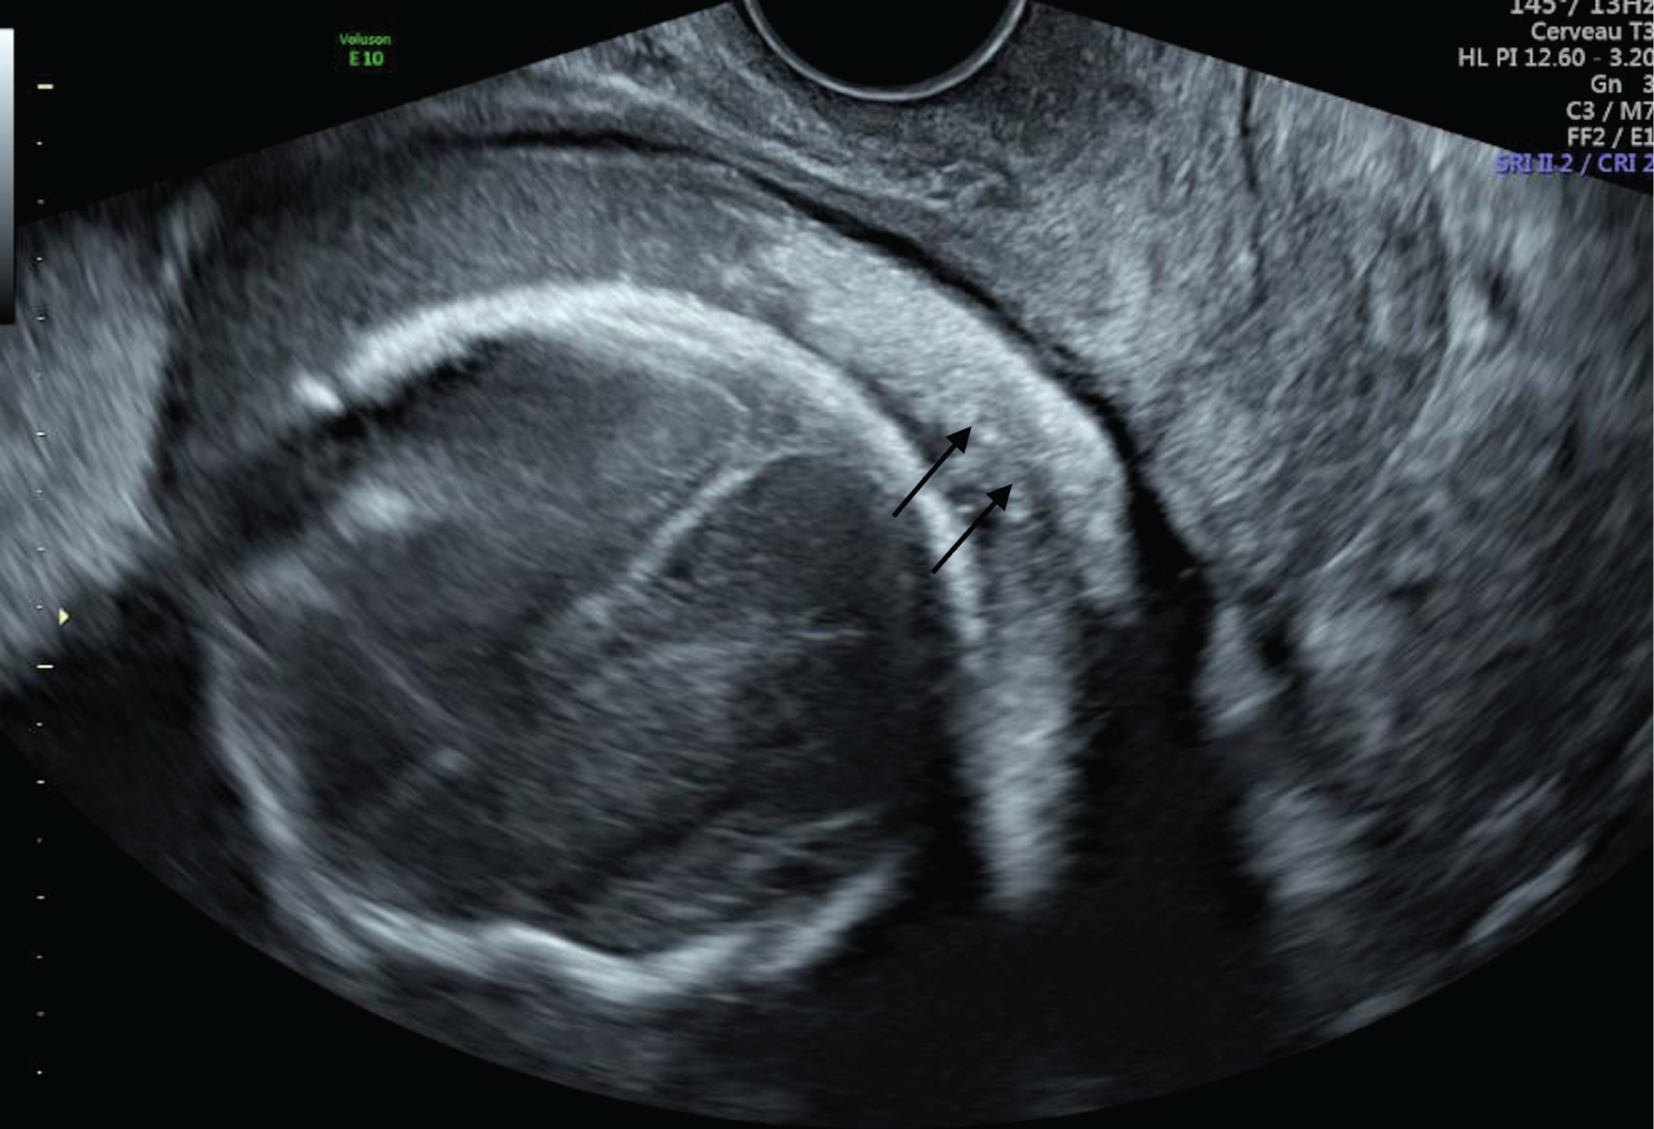

After a normal first trimester ultrasound, a 20-year-old primigravida woman was diagnosed at 27 weeks of gestational age (GA) with fetal growth restriction (FGR). The estimated fetal weight was at the 0.7th percentile. The fetus had facial dysmorphism with the mouth constantly open as an eclabium, hypoplastic nose (Figure 1), intragastric hyperechoic content (Figure 2) and skin scaling with skin particles floating in the amniotic liquid (Figure 3). The amniotic liquid was slightly hyperechoic with sedimentation of skin scales observed by vaginal ultrasound (Figure 4). No visceral abnormality was found. The amniocentesis performed showed an alpha-fetoprotein increased ten-fold (60,500 μg/L). Those findings recall a severe congenital ichthyosis and termination of pregnancy was proposed, but refused. Within several weeks we observed progressively fetal immobilism and hydramnios. At 30 weeks of GA corticosteroids prophylaxis and tocolytics were administrated to prevent premature delivery secondary to uterine contractions due to hydramnios. At 31 weeks of GA the patient gave birth to a baby boy of 1380 g, 40 cm of height and 28 cm of cranial circumference and normal cord blood pH. The Apgar score was 3–3–3. The baby boy had severe ichthyosis, atrophic ears, everted eyelids (ectropion), a hypoplastic nose, eclabium and stiffened skin surface. The couple opted for palliative care and the baby died at 33 min of life. An autopsy was refused. Comparative genomic hybridisation (CGH) array and clinical exome on cord blood were negative.

Amniotic liquid hyperechoic and skin scales sedimentation observed at vaginal ultrasound, just above the cervix (black arrows).

The most frequent signs found in these articles were FGR, facial dysmorphism with ectropion, eclabium, hypoplastic nose and flattened ears, thick skin, reduced fetal movement with eventually clubfoot, clenched fist and contractures of the limbs. The amniotic liquid was often hyperechoic with a “snowflake sign” due to skin scaling. Polyhydramnios was often associated secondary to fetal immobilism. These signs are concordant with the sonographic presentation of our case.